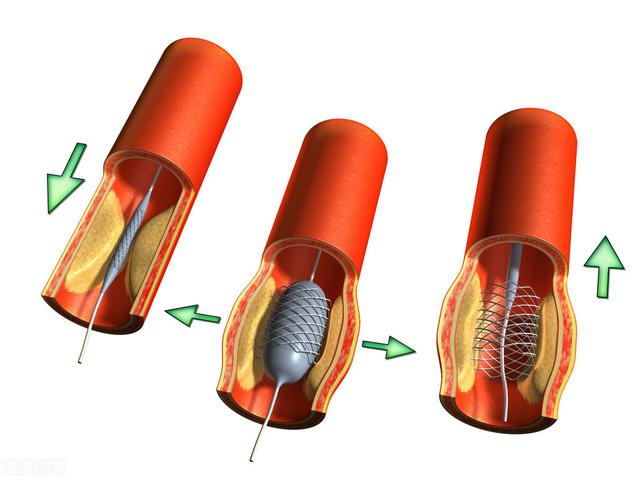

ステップ1、パンク。末梢動脈を見つけ、この動脈から穿刺を行うが、最も一般的な選択は、手の付け根か太ももの末梢動脈を選択することである。

ステップ2、チューブの挿入。その末梢血管開口部からシースを挿入し、適切なサイズのシースを選択してガイドワイヤーを進め、冠動脈開口部付近の心臓までゆっくりと送り込む。

ステップ3:軌道を確立する。最初のガイドワイヤーは冠動脈より太いので、この時は細いガイドワイヤーを選んで冠動脈病変の遠位部を通過させ、まずバルーンで拡張しなければならない。

ステップ4:ステントを留置する。バルーンの拡張が完了したら、このガイドワイヤーに従ってステントを留置する。

これが心臓ステント手術の大まかな流れだ。 経験を積んだ。熟練した医師は、この手術を30分以上かけて行う!そのため、心臓ステント手術を専門とする医師にとっては、そうである。大きな作戦ではない。。